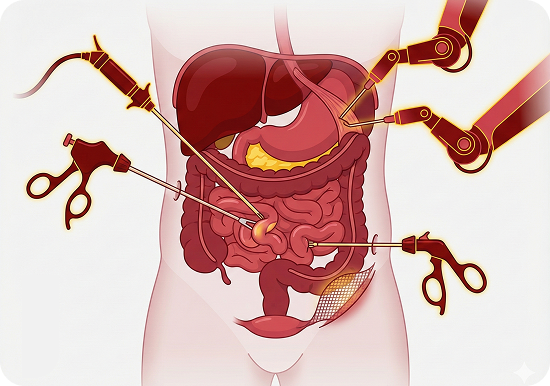

Pancreatic Surgery

- Whipple procedure (Pancreaticoduodenectomy)

- Distal and total pancreatectomy

- Minimally invasive and robotic-assisted pancreatic surgery

- Surgical management of pancreatic cysts and neuroendocrine tumour

- Vascular resections in pancreatic cancer surgery

- Surgical drainage of pancreatic pseudocysts

- Necrosectomy for infected pancreatic necrosis

- Surgery for chronic pancreatitis

Biliary & Liver Surgery

- Hepatectomy for liver tumours and metastases

- Bile duct resections and reconstructions

- Surgery for bile duct injuries, strictures, and gallbladder stones

- Management of gallbladder cancer

- Liver cyst and abscess drainage procedures

Gastrointestinal Oncology

- Surgery for stomach and colorectal cancers

- HIPEC (Hyperthermic Intraperitoneal Chemotherapy) for advanced GI cancers

- Minimally invasive and robotic-assisted pancreatic surgery

- Laparoscopic and robotic-assisted gastrointestinal surgeries

Advanced Minimal Access Surgery

- Laparoscopic and robotic gastrointestinal surgeries

- Keyhole surgery for hernia repairs (inguinal, incisional, and diaphragmatic hernias)